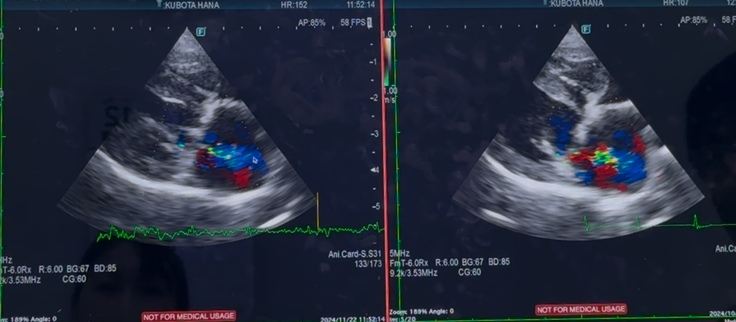

今日は、心臓手術後1年3ヶ月検診でした…

逆流は、変わらずあり…

三尖弁の逆流と肺高血圧症も

中等度と、変わらず…

心臓は、相変わらず小さくはなっておらず…

逆流も、変わらずありますが…